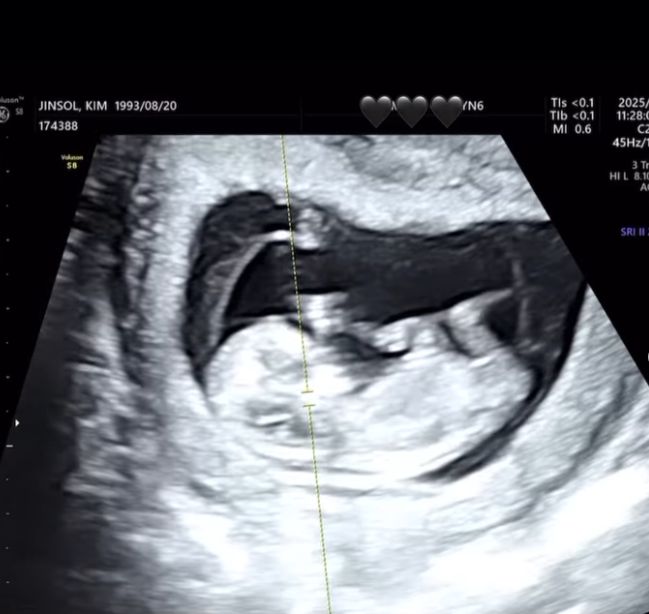

래퍼 트루디(본명 김진솔, 32)가 임신 소식을 전했다.

트루디는 9일 자신의 SNS에 “지금도 믿기지 않지만 제가 올해 11월에 엄마가 됩니다. 태명은 ‘금똥이’입니다. 배가 너무 나와서 똥인 줄 알았는데 알고 보니 금덩이더라고요. 축하해주신 모든 분들께 감사드립니다. 아직 많이 서툴지만 많은 도움 부탁드려요. 사랑해요”라는 문구와 태아 초음파 사진을 공개하고 임신 사실을 밝혔다.